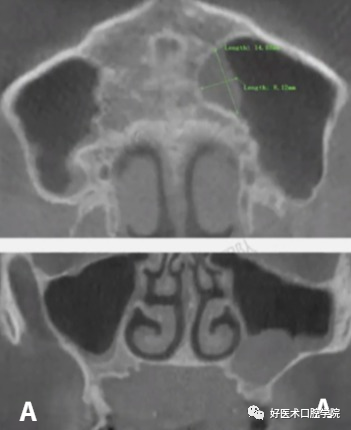

A:上颌窦粘液囊肿(周围可见骨质破坏) B:上颌窦积液(周围无骨质破坏)

上颌窦黏液囊肿多系黏液排出堵塞而使液体累积上颌窦窦口所致,囊肿内衬上皮,囊肿内充满黏蛋白,随着囊肿的增大在影像上可见病窦区密度增高,呈膨胀性扩大,多呈圆形膨隆,有时可见反应白线,囊肿周围出现骨质破坏,骨上颌窦壁轻度硬化或压迫性吸收和损伤邻近组织,患者通常会出现疼痛、肿胀、鼻塞等症状。

CT扫描用增强对比的方法可与恶性肿瘤相鉴别,恶性肿瘤在注射泛影葡胺增强剂后有不同程度的增强,囊肿仅在囊壁周围有所增强。

上颌窦粘液囊肿在我国发病率较低,据统计,仅占鼻窦粘液囊肿的3%~10%。